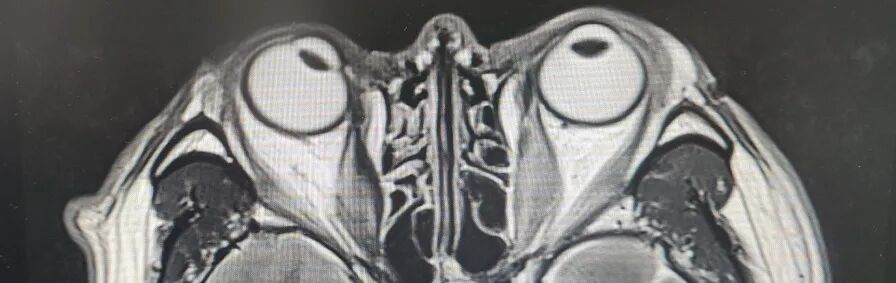

引言 生活中,很多人会突然出现“看东西重影”的情况,往往以为是眼睛疲劳或近视加深,并没有太当回事。然而,这背后可能隐藏着甲亢、脑梗、重症肌无力甚至肿瘤等十余种疾病的信号,是一个需要警惕的“隐形杀手”。 面对这类病因错综复杂的“复视”患者,市二院神经内二科赵智江主任带领团队,凭借丰富的临床经验和深厚的神经疾病诊疗功底,抽丝剥茧,多次成功揪出导致视物成双的“真凶”,为患者赢得了宝贵的治疗时机。 Part.01 复视背后,病因五花八门 神经内二科团队诊治了多位以“视物成双”为主诉的患者,其最终病因各异,充分体现了神经科疾病“同症异源”的复杂性。 以为是眼病,其实是甲亢 患者因复视就诊,经查双眼突出,影像检查发现控制眼球的肌肉异常肥厚。结合甲状腺功能检查,最终确诊为“甲亢性眼肌病”,其原因在甲状腺功能亢进的眼部表现。后经针对性纠正甲状腺功能,患者复视症状显著改善,眼外肌肥厚得到有效控制。 眼眶核磁 甲功结果 眼球状态 复视眼痛,原是痛性眼肌麻痹 患者右眼不仅看东西重影,还出现上睑下垂、眼痛等症状。团队排除其他可能后,诊断为痛性眼肌麻痹(Toloas-Hunt综合征),这是一种自身免疫性炎症。经治疗,患者眼睑下垂症状减轻,眼痛及复视基本消失,眼球运动范围显著恢复。 梅毒隐匿,损伤颅神经 患者因眼皮抬不起、眼球转动不灵并视物重影入院。常规血清检查发现梅毒抗体阳性,排除其它原因导致的复视,最终明确为“神经梅毒”侵蚀颅神经所致。确诊后立即给予驱梅治疗,效果明显,眼皮能抬起来了,重影消失了,眼球转动也灵活了。 糖尿病悄悄损伤神经 两位糖尿病患者,均以突发复视就诊。团队精准判断,发现分别是高血糖损伤了“动眼神经”和“外展神经”,属于糖尿病性单神经病变,表现为不同类型的复影(上下重影或水平重影)。明确诊断后,经严格控糖,辅以营养神经药物等综合对症治疗,患者病情好转,顺利出院。 脑梗“瞄准”不同区域 三位患者均因复视就诊,但伴随症状各异,有的行走不稳,有的走路右偏。赵智江主任团队通过精细的神经系统查体,精准定位于中脑的动眼神经核、桥脑的内侧纵束等。不同脑区梗死,复视的表现也完全不同。后通过溶栓药物、抗血小板药物、改善循环治疗等针对性治疗,辅以康复治疗,患者身体逐渐好转,出院时已无视物成双症状。 三位患者的核磁 典型信号——晨轻暮重 患者出现复视,伴言语不利、吞咽困难、饮水呛咳等症状。其中复视有个鲜明特点——早晨轻、傍晚重,疲劳后加重。经专项检查,确诊为“重症肌无力”(眼肌型)。这是一种神经肌肉接头疾病,免疫调节治疗可有效控制。经过一段时间的治疗,患者复视症状明显缓解,言语不清、吞咽困难症状得到显著改善。治疗前患者只能进食流食,治疗后可自主进食固体食物。 肿瘤病史者,需警惕转移 淋巴瘤患者在化疗期间出现复视和面瘫。团队通过脑脊液等深入检查,排除感染等因素,最终诊断为脑膜癌病。 嗜睡头晕,病因在营养 患者急性起病,表现为复视、头晕、嗜睡、走路不稳。团队结合其既往史和典型眼球活动障碍,迅速锁定病因——因维生素B1严重缺乏导致的“韦尼克脑病(Wernicke)”。补充维生素B1一周以后,患者复视症状改善、走路平稳、神志清楚,可独立行走。 Part.02 精准诊疗,揪出“元凶”是关键 赵智江主任指出:“复视只是一个临床症状,其背后可能是内分泌、炎症、代谢、脑血管、自身免疫、肿瘤等多种病因在神经系统上的投射,涉及学科广泛。” 市二院神经内二科团队通过详细追溯病史、进行一丝不苟的神经系统专科查体(尤其是眼球运动检查),初步判断病变可能位于动眼、滑车、外展神经的神经核团,神经及其所支配的肌肉、神经-肌肉接头等部位,然后精准选择并解读影像学、免疫学、生化及脑脊液等检查结果,最终整合信息,明确诊断,为患者制定出针对性的治疗方案。 市二院神经内二科在赵智江主任的带领下,始终致力于复杂疑难神经系统疾病的诊疗攻坚。科室凭借严谨的临床路径、对神经解剖与病理生理机制的深刻把握,以及精湛的诊疗技术,为众多罕见病与危重患者精准定位病因、制定个体化治疗方案,有效提升了救治成功率与患者长期生活质量。 提醒市民:如果突然出现视物重影,尤其是伴有眼皮下垂、眼球转动不灵、疼痛、头晕、行走不稳或其他神经系统症状时,切勿掉以轻心,应及时重视,这些症状有时可能与神经系统疾病相关。为了明确原因,获得更全面的评估,您可以考虑到神经内二科就诊,由专业医生进一步检查与诊断,以便尽早获得适合的照顾与治疗。 Part.03 人民医院 人民名医 赵智江 主任医师 副教授 ·葫芦岛市第二人民医院神经内二科主任 ·中国卒中学会高级会员 ·中国老年保健医学研究会老年脑血管病分会委员 ·北京神经内科学会脑小血管病学会委员 ·安徽医药杂志审稿专家 ·辽西神经疾病专科联盟理事 ·辽西认知功能障碍联盟理事 ·辽西神经免疫学会委员 ·葫芦岛市医学会神经病学分会委员 专业特色:以脑血管病为核心研究方向,擅长各类神经系统疾病的诊疗,尤其在脑血管病、帕金森综合征、头晕、头痛、癫痫、重症肌无力、多发性硬化等神经免疫性疾病以及其它神经系统疑难、危重疾病的诊疗方面积累了丰富的临床经验。 出诊时间:每周一、周四全天 咨询热线:0429-8010317